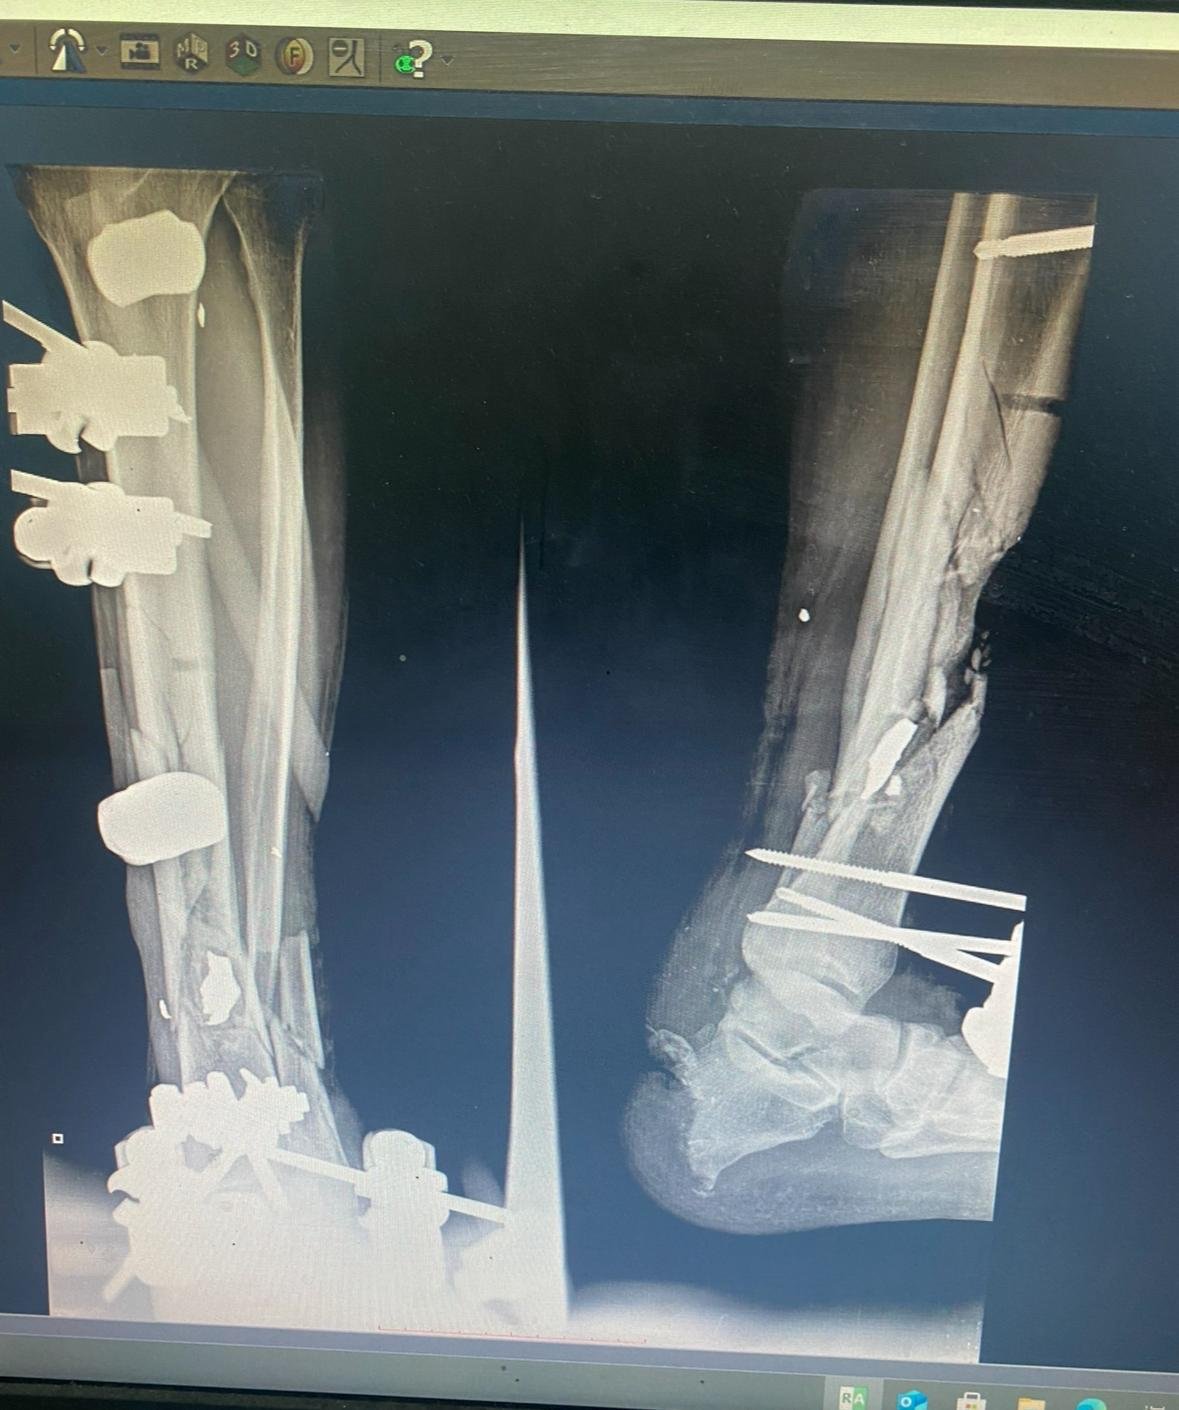

Every one of the patients stated they were waiting in line in the sun (100+ degree F weather) until quadcopters came flying overhead and then they lowered and began firing at all their legs. Many ran, some were trampled, and some were hit by quadcopter fire. The injured that survived ended up on the floor of the ER writhing in pain in an environment with no morphine, limited blood products and no sterility. Tibias and femurs shatter by gunfire and a few vascular injuries putting limbs at risk for amputation.